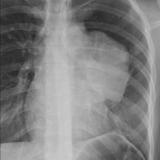

Case 8b Thymoma Lat

Date: 03/27/2009

Views: 14175